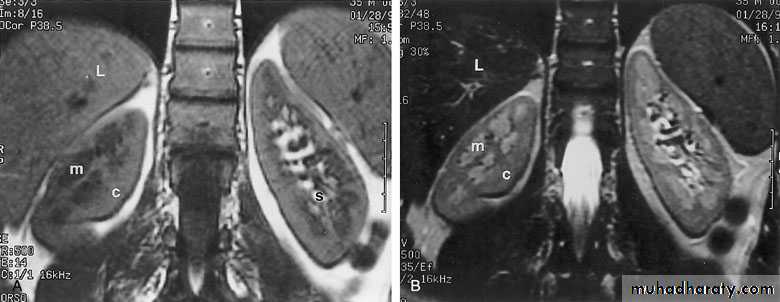

MAGNETIC RESONANCE IMAGING (MRI)Protons within the body can be thought of as small, spinning bar magnets. Hydrogen has a single proton. When a patient is placed in a large magnetic field, the hydrogen protons within the body align, and this alignment leads to the formation of a net magnetic vector within the patient.

Contrast: Gadolinium

No

radiation